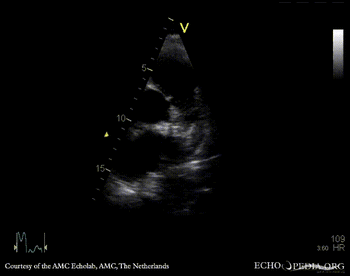

| Courtesy of: AMC Echolab, AMC, The Netherlands | |

| Suprasternal view | Suprasternal view |